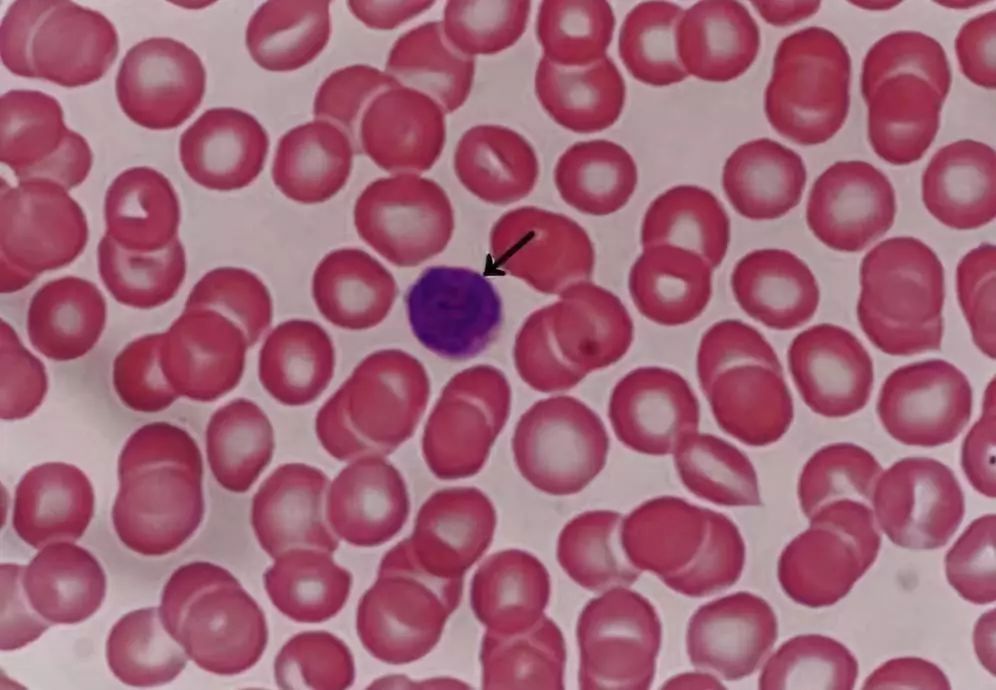

图1. 血涂片光镜像(Wright 染色)

箭头指示的是中性粒细胞。为球形细胞,直径10-12μm,分叶核,胞质粉红色,内含细小的,分布均匀的淡紫色和淡红色颗粒。

图2. 血涂片光镜像(Wright 染色)

箭头指示的是淋巴细胞(小淋巴细胞),球形细胞,直径6-8μm,与红细胞直径相仿。核圆形,染色深,一侧常有小凹陷,胞质很少,染成天蓝色。